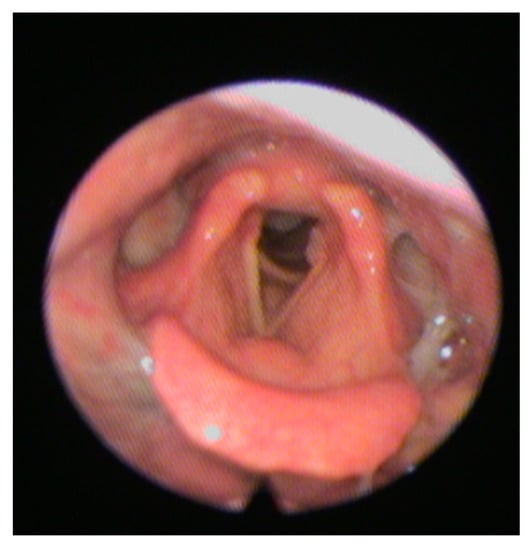

- Langmore, S.E.; Schatz, K.; Olsen, N. Fiberoptic endoscopic examination of swallowing safety: A new procedure. Dysphagia 1988, 2, 216–219. [Google Scholar] [CrossRef]

- Checklin, M.; Dahl, T.; Tomolo, G. Feasibility and Safety of Fiberoptic Endoscopic Evaluation of Swallowing in People with Disorder of Consciousness: A Systematic Review. Dysphagia 2021, 1–10. [Google Scholar] [CrossRef] [PubMed]

- Kelly, A.M.; Leslie, P.; Beale, T.; Payten, C.; Drinnan, M.J. Fibreoptic endoscopic evaluation of swallowing and videofluoroscopy: Does examination type influence perception of pharyngeal residue severity? Clin. Otolaryngol. 2006, 31, 425–432. [Google Scholar] [CrossRef]